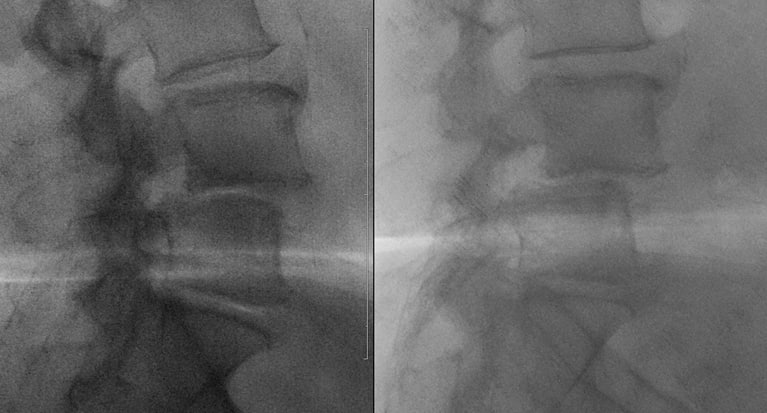

Пациент делает рентгеновские снимки не просто стоя, а в максимальном наклоне вперед и назад. Это показывает, как ведут себя позвонки в движении. Смещение, которое было незаметно в статике (на МРТ или КТ), может явно проявиться при сгибании-разгибании.

Бывает, что спондилолистез, четко видимый на МРТ, оказывается стабильным на функциональных снимках — то есть позвонки не «ездят» друг относительно друга при движении. И наоборот, вроде бы небольшая проблема на МРТ может маскировать серьезную нестабильность.

Именно сочетание жалоб пациента и данных функциональной рентгенографии часто становится решающим аргументом в пользу операции, например, для установки системы стабилизации (металлофиксации).